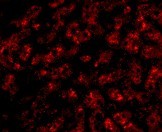

Supportive validation

- Submitted by

- Acris Antibodies GmbH (provider)

- Main image

- Experimental details

- Immunofluorescence of ApoA1 in human liver tissue with AP30068PU-N ApoA1 antibody at 20 μg/ml.